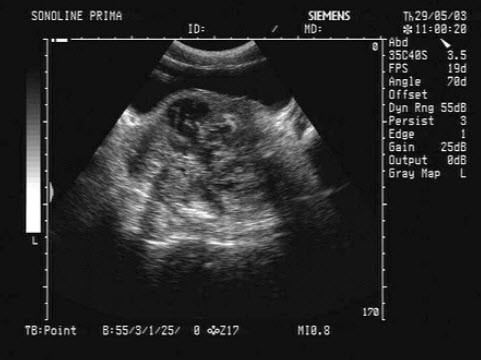

52、单项选择题

女性,29岁,停经28周,产前超声检查如图,最可能的诊断为()